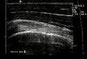

Mit unserem modernen Ultraschallgerät können wir Gelenke, Muskeln und Sehnen untersuchen und rasch feststellen, ob ein Muskel eingerissen ist, das Hüftgelenk einen Erguß hat oder der Knorpel rheumatisch geschädigt ist. Wir können auch gezielte Punktionen hiermit vornehmen - alles ohne Strahlenbelastung.